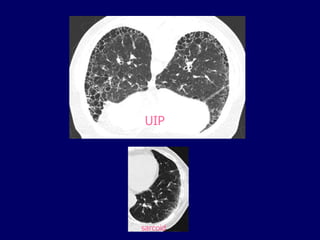

UIP

basal subpleural

honeycombing*

*not merely reticular pattern, check density within cystic

air spaces

Usual Interstitial Pneumonia

HRCT Findings

Reticular opacities, thickened intra- and

interlobular septa

Irregular interfaces

Honey combing and parenchymal distorsion

Ground glass opacities (never prominent)

Basal and subpleural predominance

Basal and subpleural

distribution